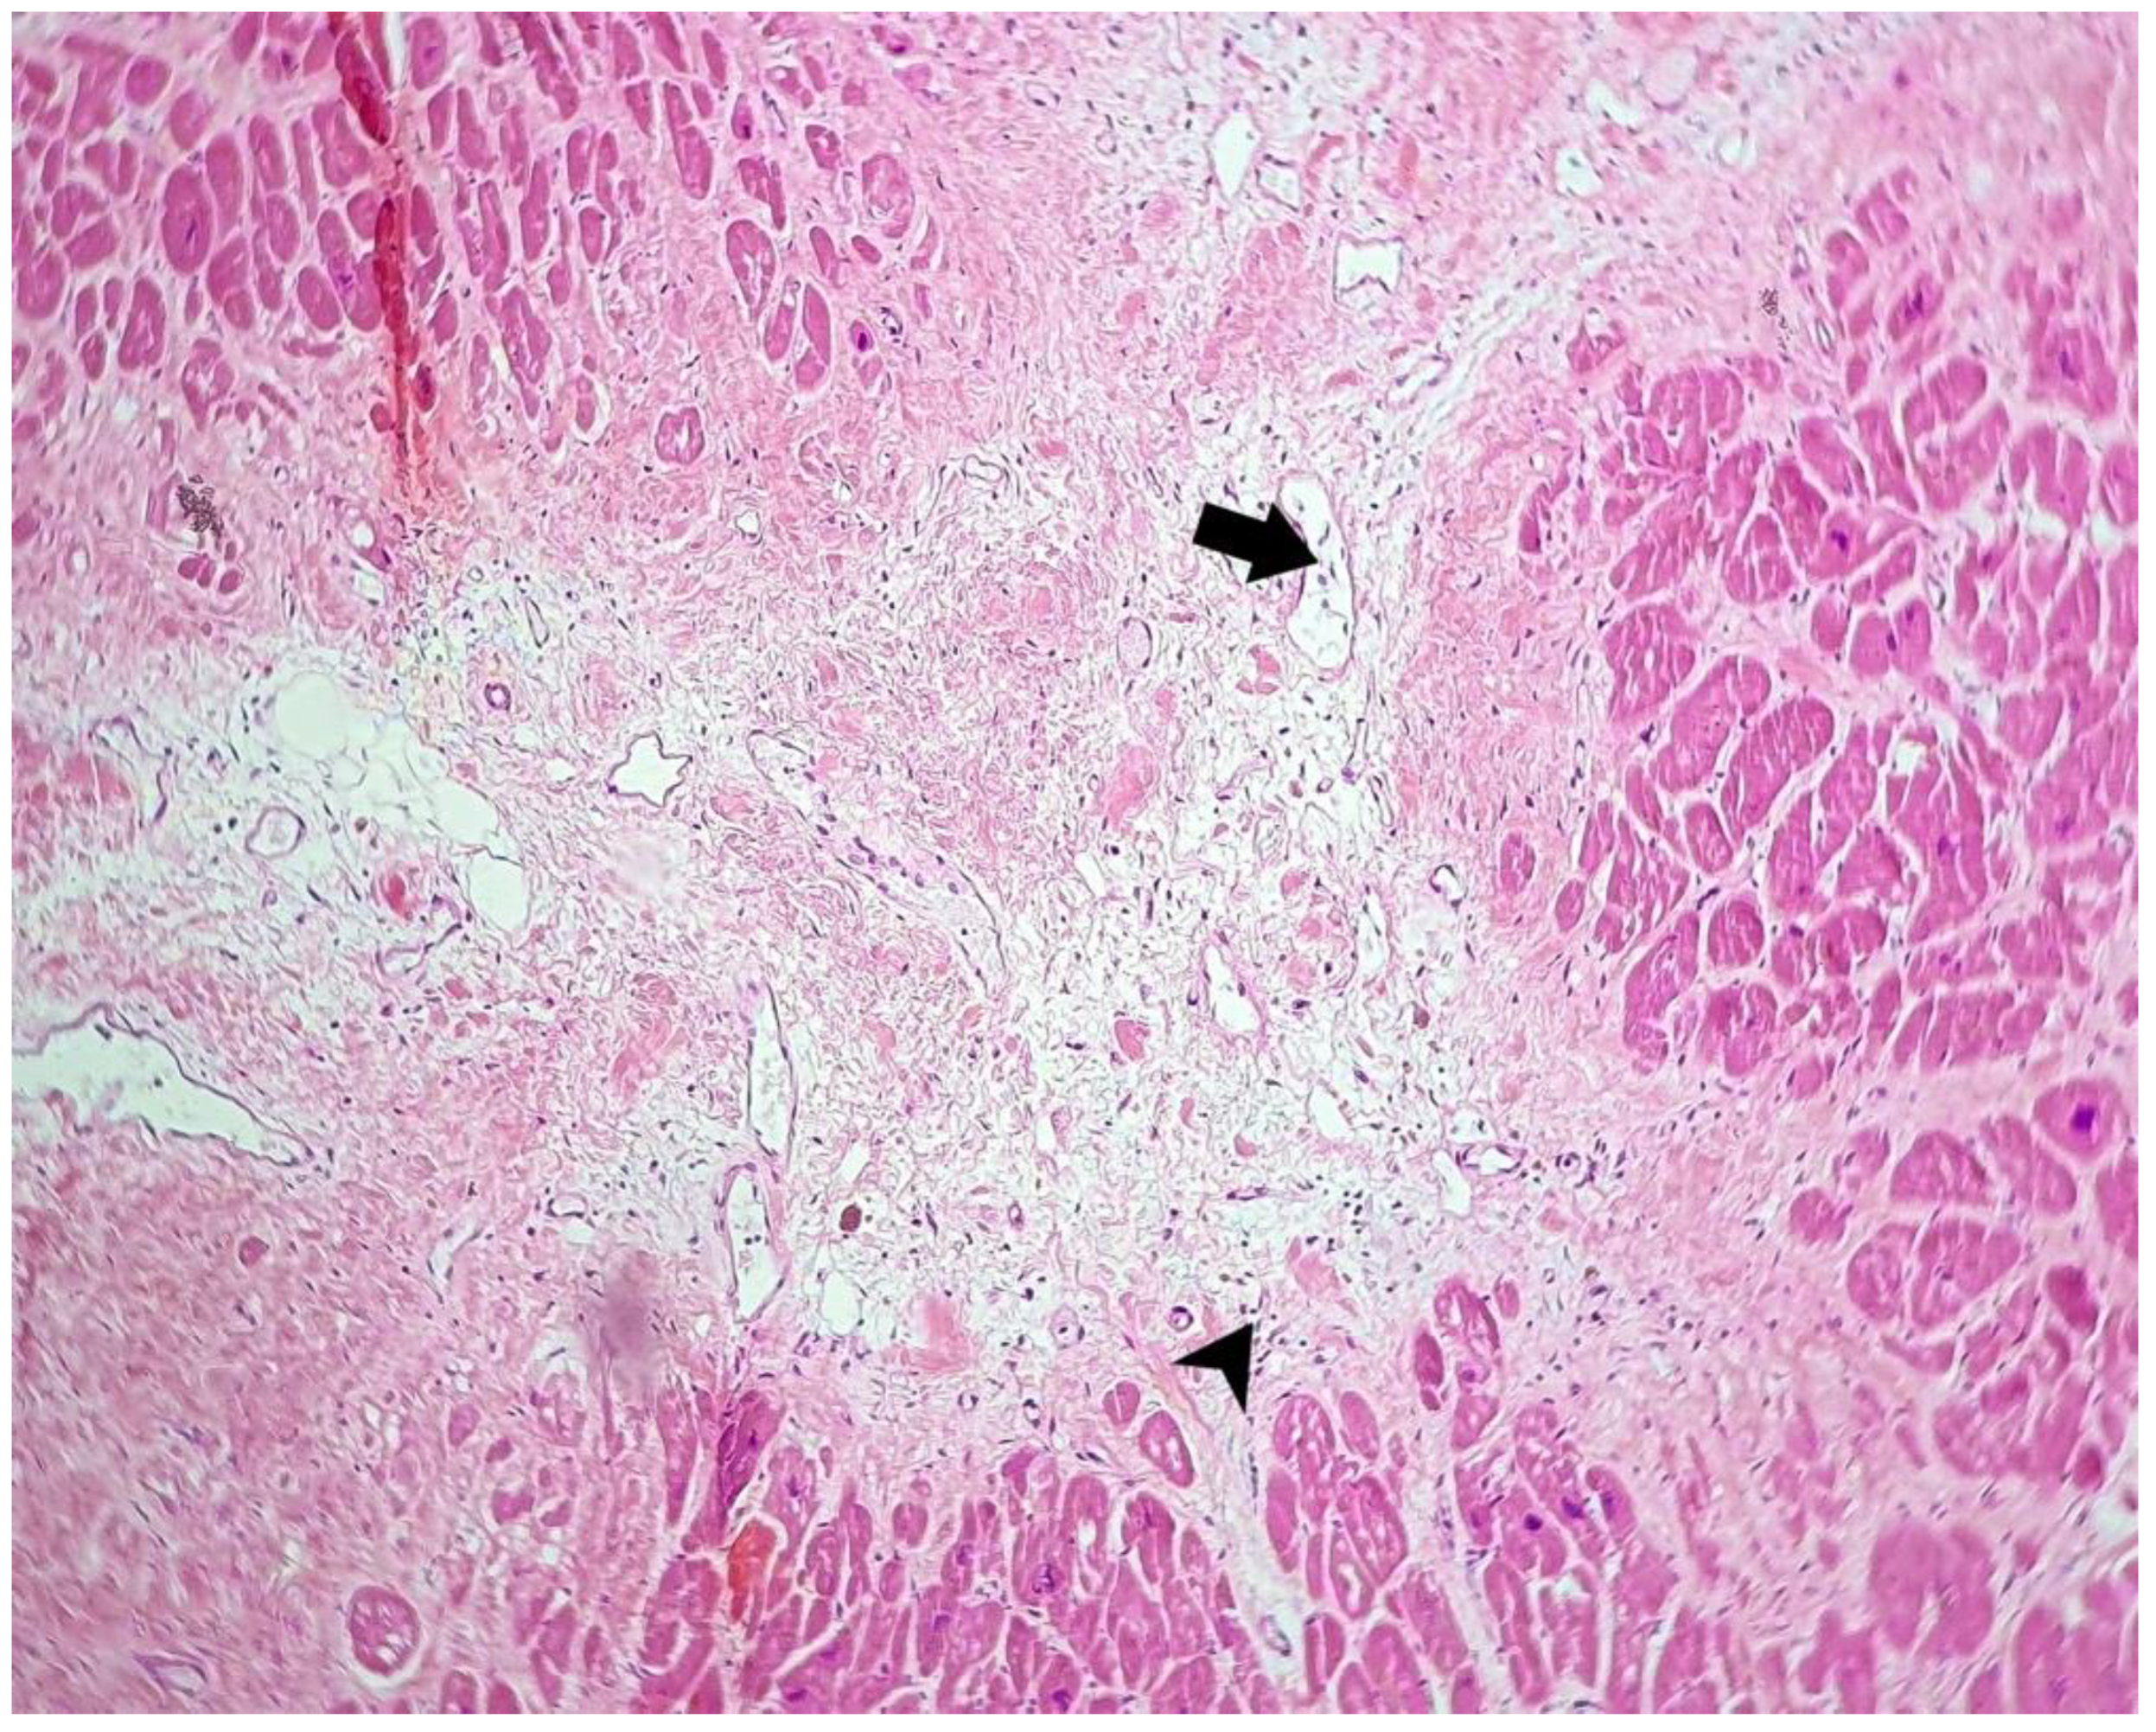

- In one case (with positivity for SARS-CoV-2 antibody), we observed a large area of myocardial necrosis with enucleated muscle fibers, eosinophilia, extravasated erythrocytes, scattered lymphocytes, neutrophils, and necrotic debris, with a halo of granulation tissue composed of newly formed capillaries, macrophages, and lymphocytic infiltrate.

| Case no. 6 | Rich diffuse inflammatory lymphocytic infiltrate in the subepicardial space visceral pericardium, with focal fibrin deposits on the surface Large extended areas of fibrosis interposed between myocardial fibers, sequestrating groups or individual myocytes, with thick, poorly cellularized, horizontally-arranged collagen fibers. In these patches of fibrosis, there is a more myxoid appearance, with an increased number of blood vessels and with a perivascular scattered lymphocytic infiltrate Small, poorly-defined areas of myocardial fibers with cytoplasmic vacuolation, nuclear pyknosis, apoptosis, and necrotic debris between these fibers Undamaged myocytes near the fibrotic patches suffered nuclear enlargement, with irregular borders and granular fine dispersed chromatin, a sign of cellular suffering Severe atherosclerosis of the coronary arteries with secondary subocclusion Large area of myocardial necrosis with enucleated muscle fibers, eosinophilia, extravasated erythrocytes, scattered lymphocytes and neutrophils and necrotic debris, with a halo of granulation tissue composed of newly-formed capillaries, macrophages, and lymphocytic infiltrate |